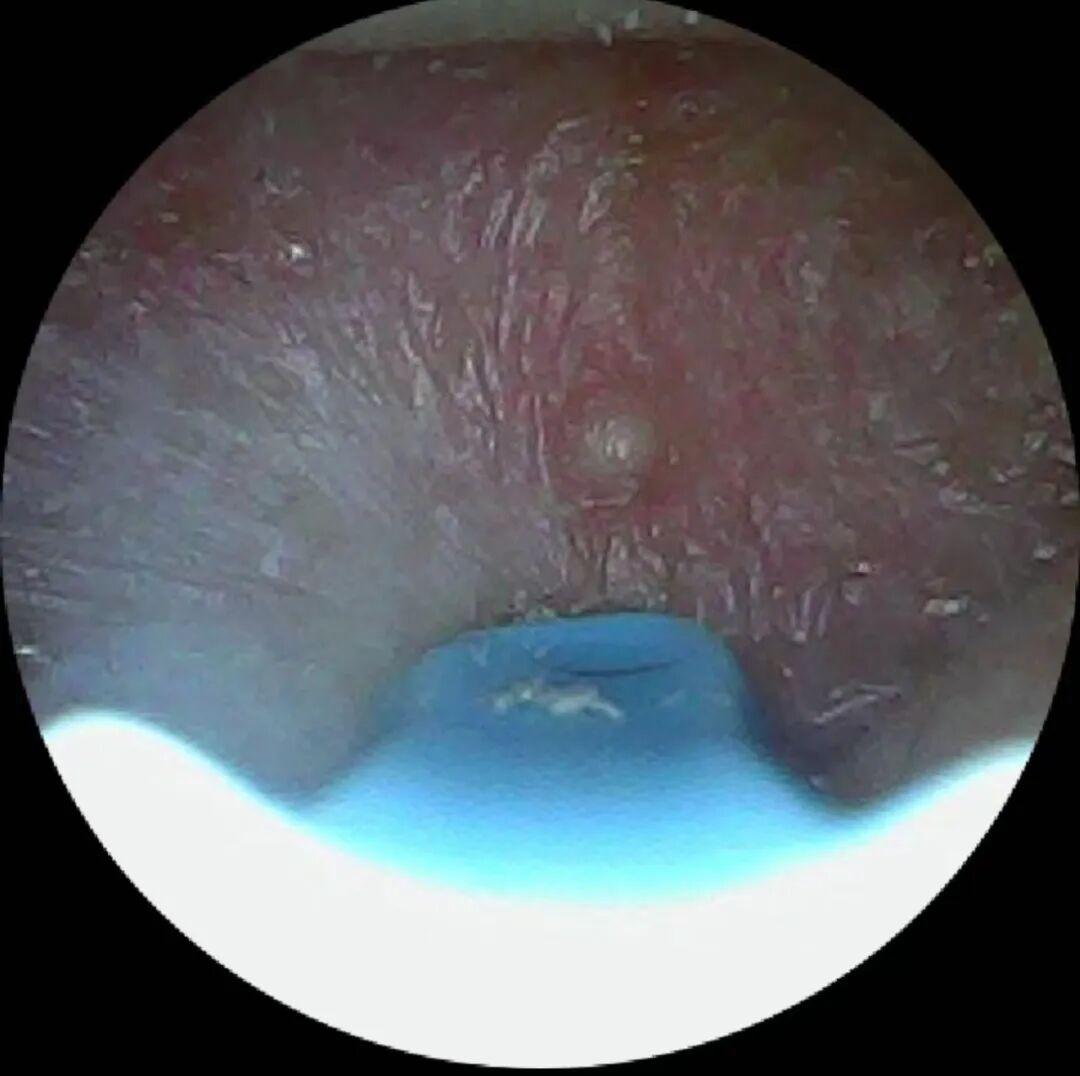

▲可視畫面

它的可視畫面是蘋果、安卓手機都可以連接的,wifi直連非常方便,超高清內窺鏡,耳道里面看得一清二楚。

拼夕夕上買的這款可視挖耳勺徹底終結了我的焦慮,它自帶1080P高清攝像頭和6顆LED無影補光燈,連上手機APP就能將耳道內的情況看得一清二楚。